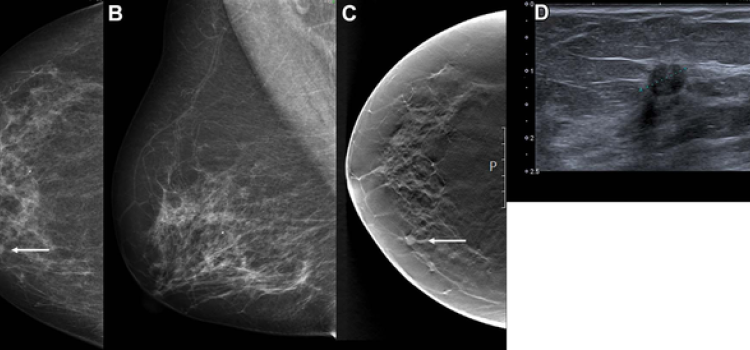

Breast density, or fibroglandular density, is found through breast imaging and compares the amount of fat to the amount of tissue.

May 13, 2025 — In one of the larger studies of its kind, researchers have identified six breast texture patterns that ...